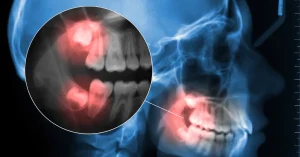

Wisdom teeth — the third set of molars — usually appear between ages 17 and 25. For many adults, these teeth grow in crooked, partially erupt, or become trapped under the gums (known as “impacted”).

- Damage bone or nerves near the jaw